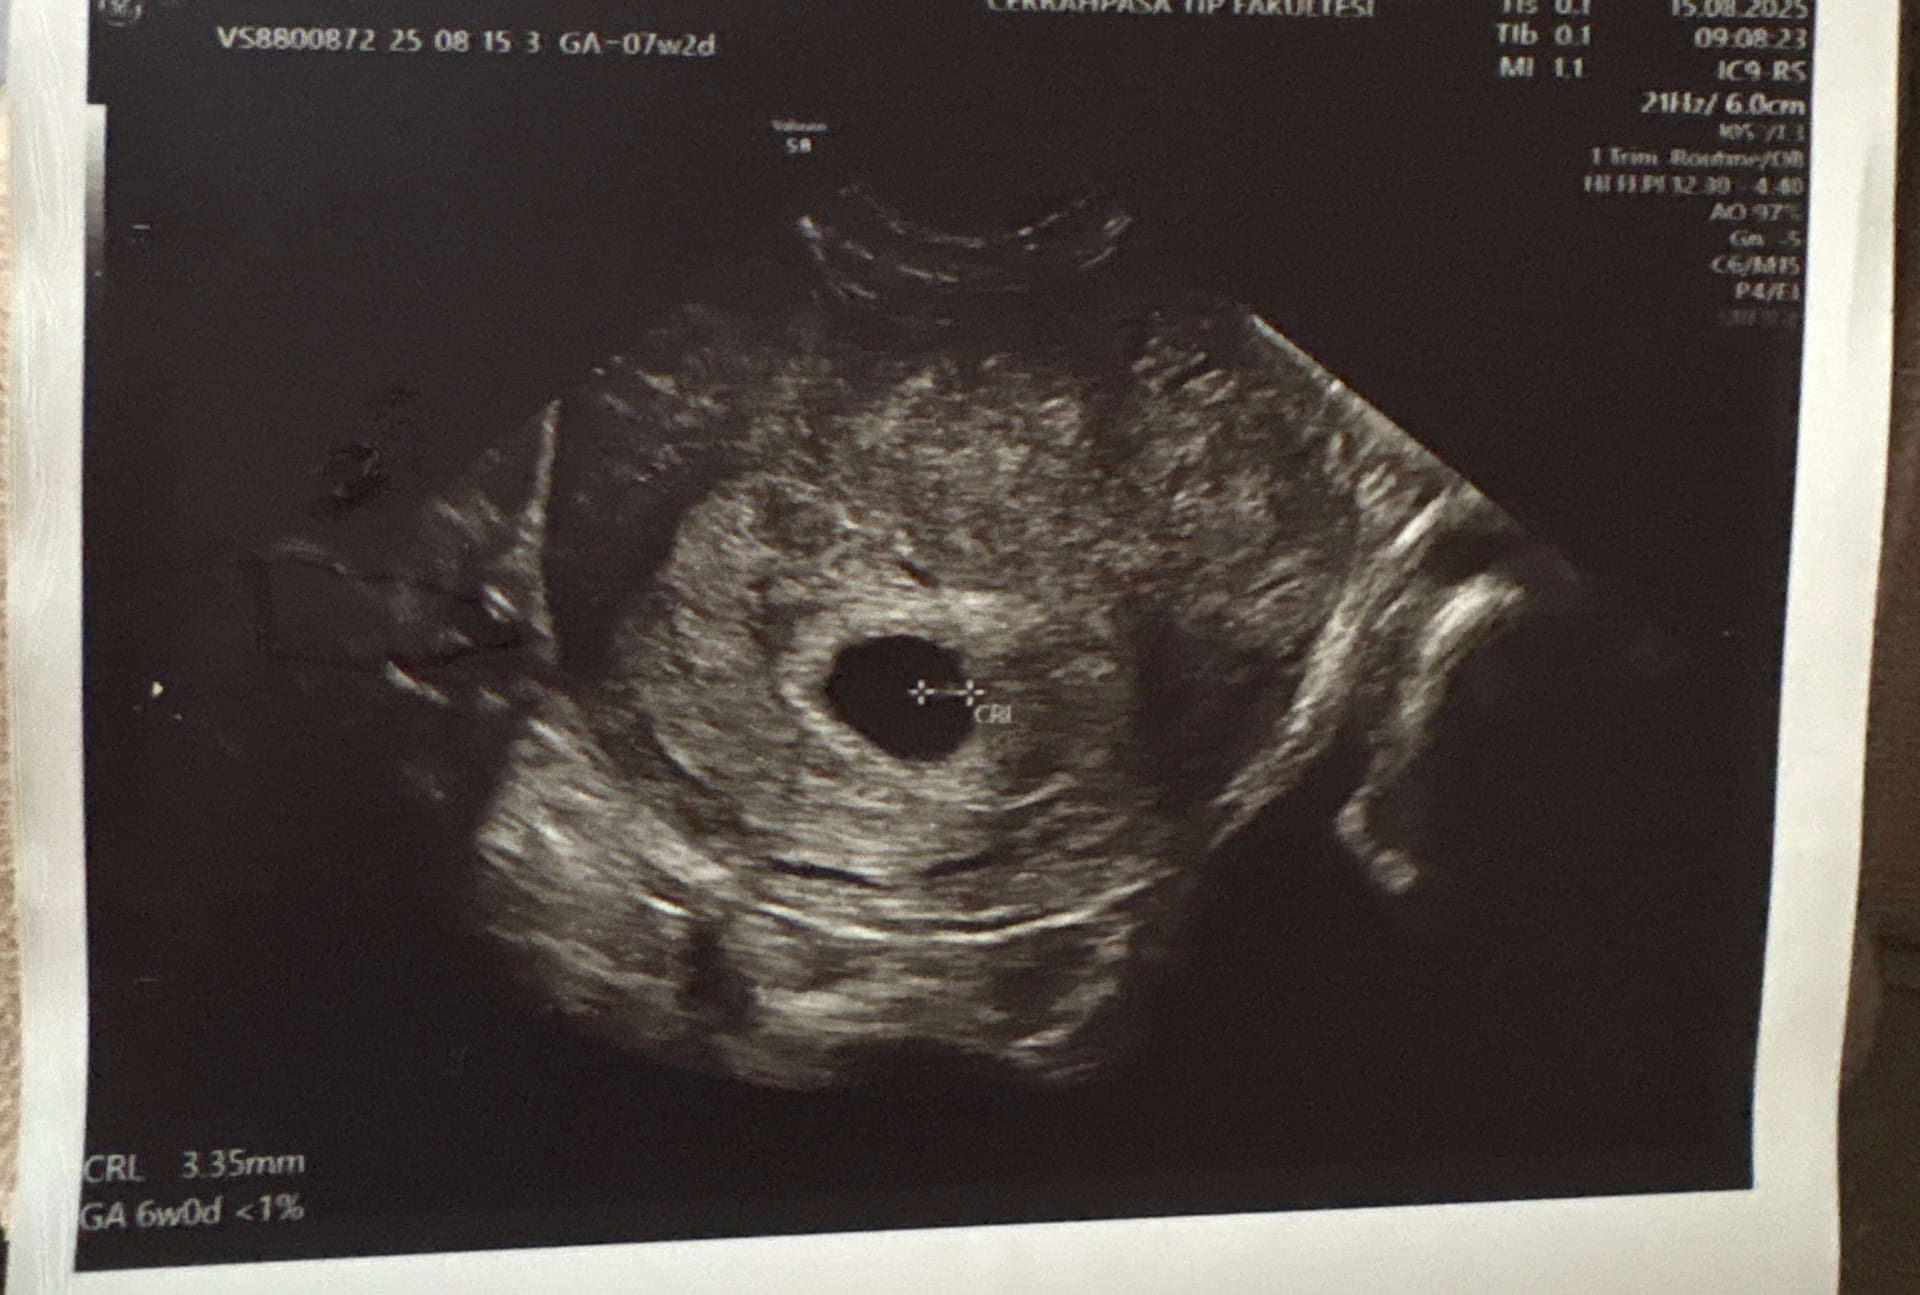

Görüntü ve Ölçüm

- Görüntüde CRL (Crown-Rump Length) yani bebeğin baş-popo uzunluğu 3.35 mm yazıyor. Bu ölçüm yaklaşık 6 hafta civarına denk geliyor.

- Rapor da zaten “GA 6w0d” (gebelik yaşı 6 hafta 0 gün) diye belirtmiş.